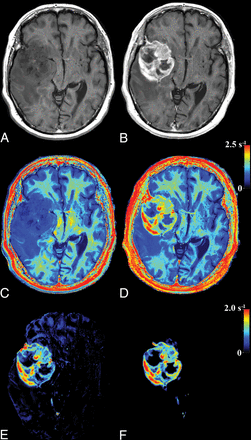

The parametric representation of R1 enhancement due to GBCA is illustrated in Fig 1. In Fig 1A, the R1 and PD values of a slice of a brain are plotted before GBCA administration. It can be clearly seen that the relation between R1 and PD for the entire brain parenchyma is approximately linear, as indicated by the gray line. In Fig 1B, the same slice is depicted after GBCA administration. The R1 values within an enhancing part of the tumor have shifted to much higher values, substantially beyond the normal, native R1–PD combinations. The rest of the brain remains largely unchanged. The synthetic R1 enhancement map is calculated using the difference of post-GBCA R1 values and the estimated native R1 values on the predetermined line. In Fig 2, the same slice of the brain is shown. Synthetic T1-weighted images (A and B) are generated using the R1, R2, and PD maps of the quantification sequence. The enhancement due to administration of GBCA is clearly visible on the T1-weighted images, as well as on the R1 maps (C and D). The native R1 maps are coregistered to the post-GBCA R1 maps to obtain the subtraction R1 enhancement (E). High-intensity enhancement corresponds to a dR1 in the range of 1.5–2.5 seconds−1. The diffuse signals throughout the entire volume are due to imperfect image coregistration of the anatomic details. In Fig 2F, the synthetic R1 enhancement map, based on the post-GBCA acquisition only, is shown. Linear regression of the subtraction and synthetic R1 enhancement maps on all patients showed a mean slope of 1.02 ± 0.19 and mean intercept of 0.05 ± 0.12. Statistically, the unity line at intercept zero could not be ruled out. The mean Pearson correlation coefficient of all patients was 0.861 ± 0.059. The mean coefficient of variation of all patients was 0.18 ± 0.04. In Fig 3, a 2D histogram is plotted of the detected R1 enhancement using subtraction of the native and post-GBCA R1 maps as a function of synthetic R1 maps for all included patients.

Images of the same slice as in Fig 1: synthetic T1-weighted imaging using native data (A), synthetic T1-weighted imaging using post-GBCA data (B), the native R1 map (C), the post-GBCA R1 map (D), the difference map of the coregistered native map (E), and the post-GBCA R1 synthetic-difference map based on the post-GBCA acquisition only (F).